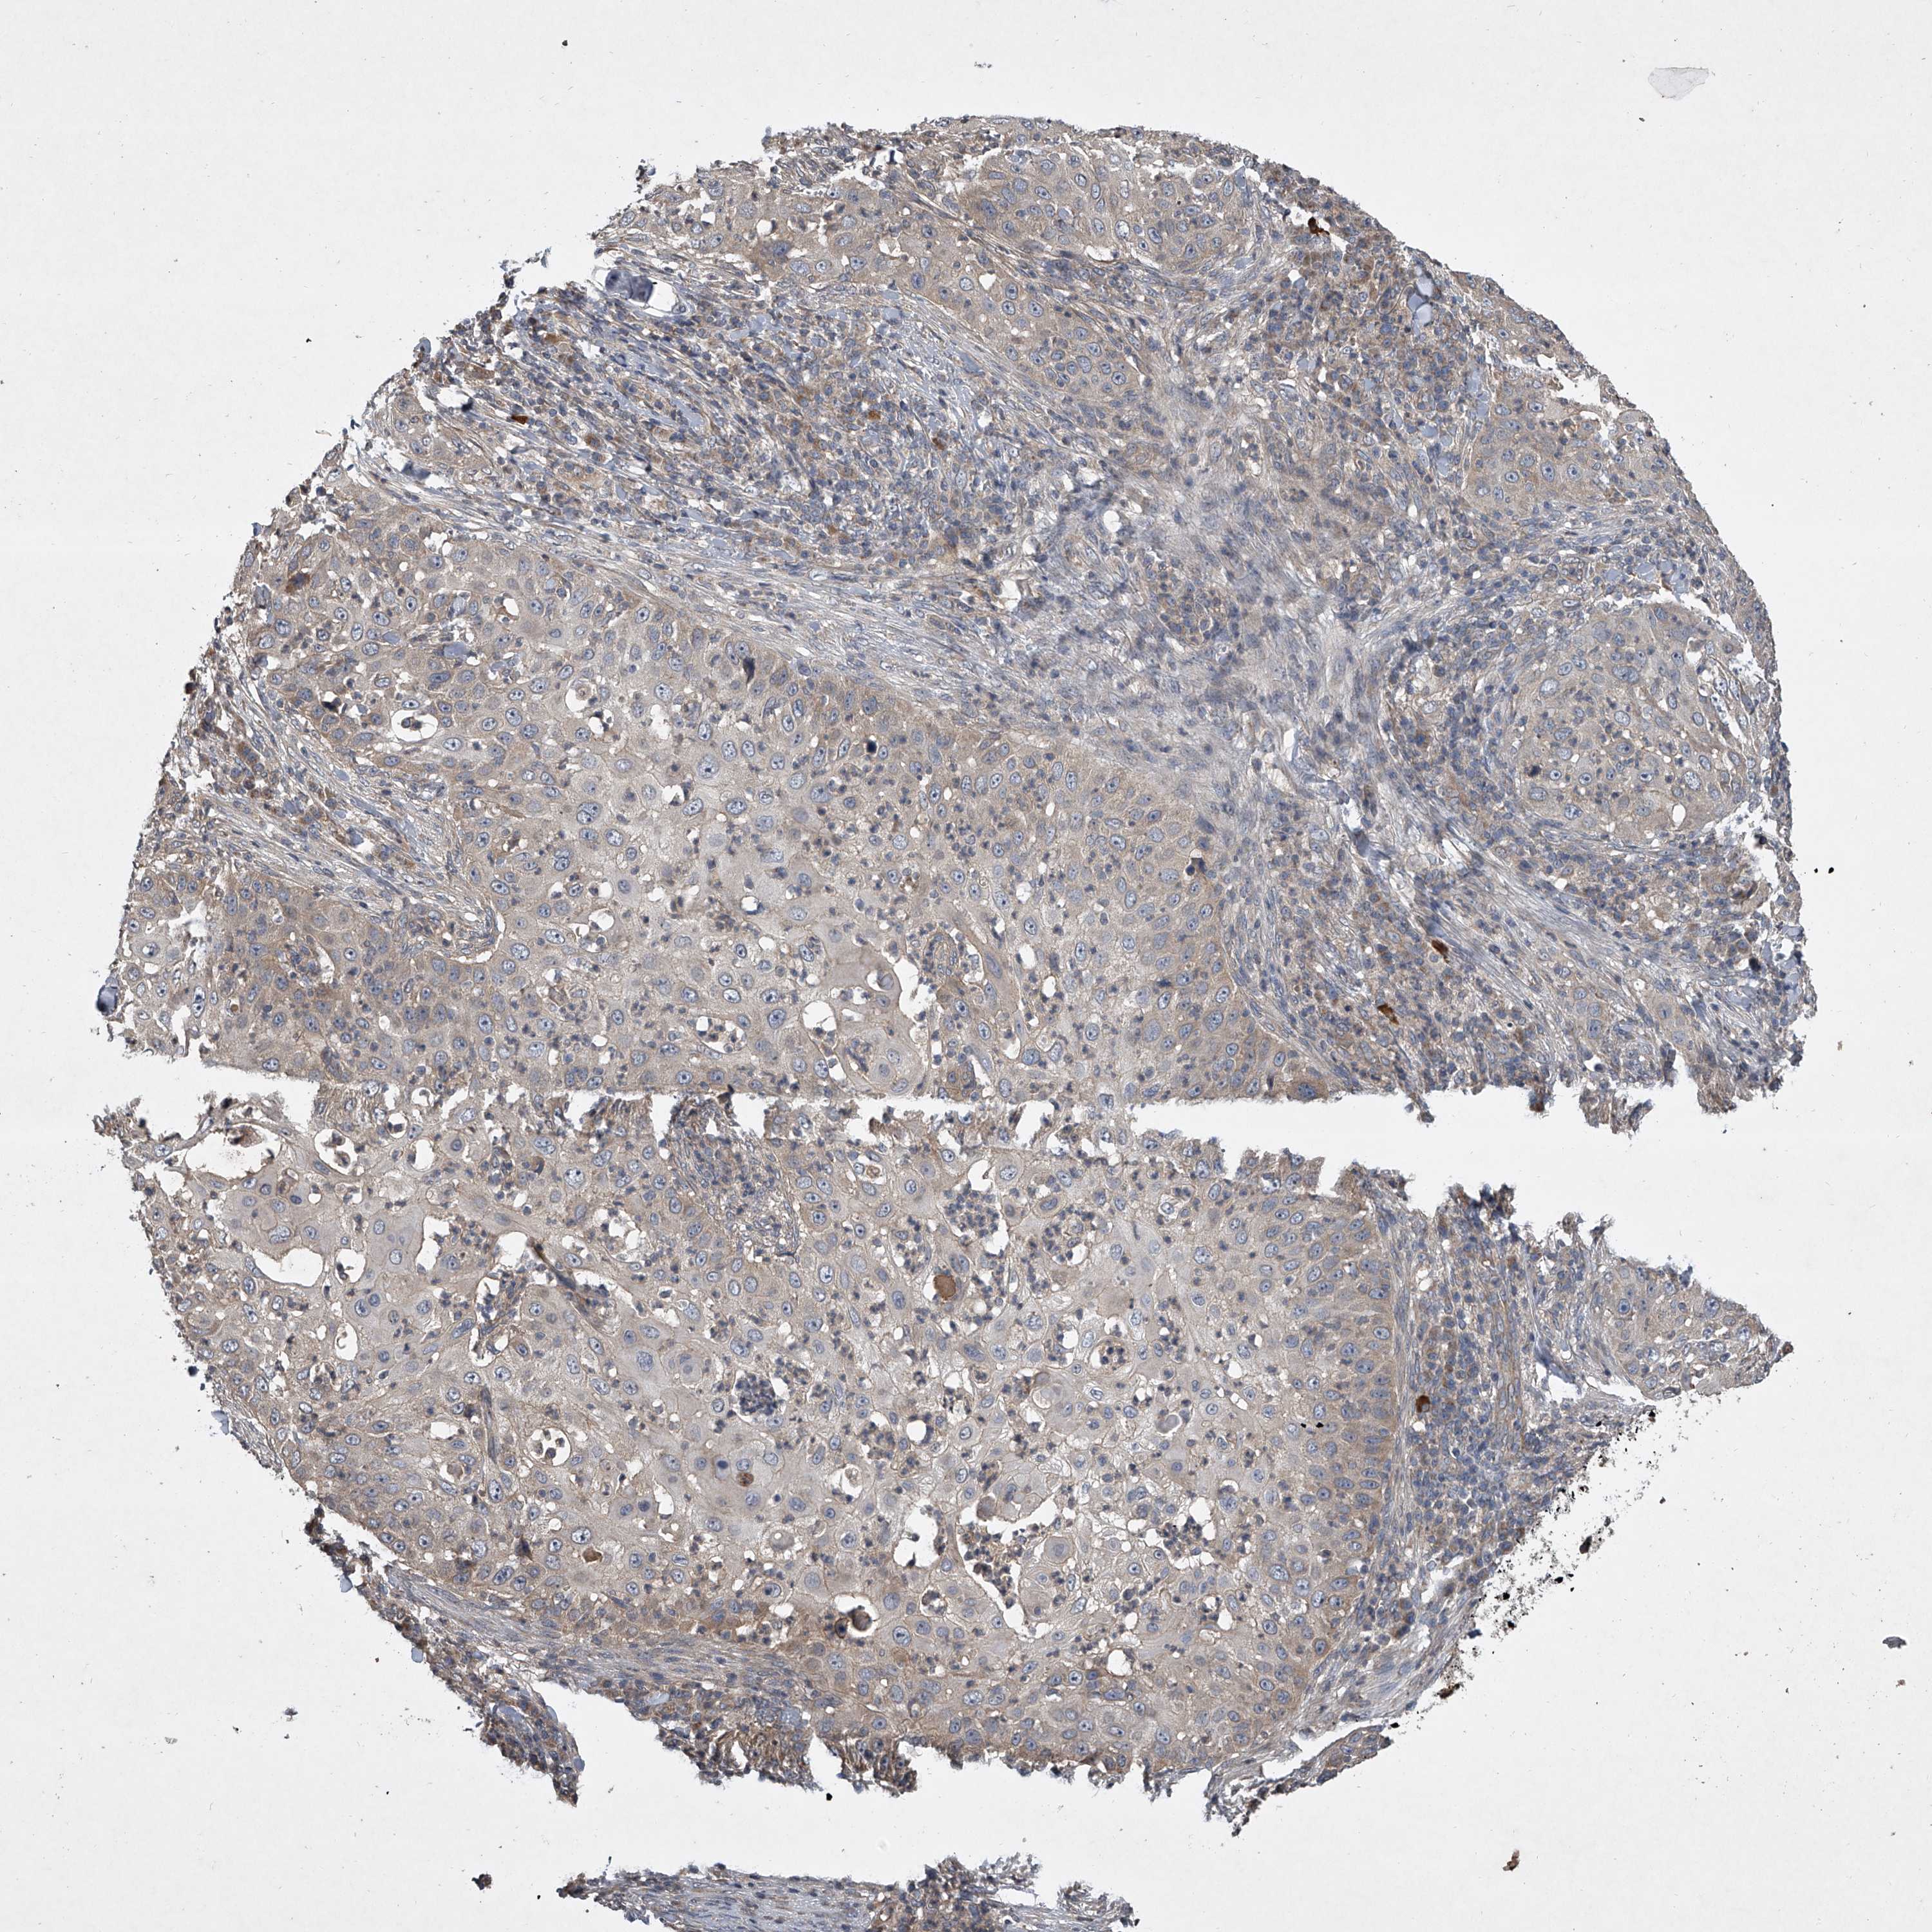

SKIN CANCER - Protein expressioni

A mouse-over function shows sample information and annotation data. Click on an image to view it in a full screen mode. Samples can be filtered based on level of antibody staining by selecting one or several of the following categories: high, medium, low and not detected. The assay and annotation is described here.

Antibody staining in the annotated cell types in the current human tissue is reported as not detected, low, medium, or high, based on conventional immunohistochemistry profiling in selected tissues. This score is based on the combination of the staining intensity and fraction of stained cells.

Each image is clickable and will lead to virtual microscopy that enables deeper exploration of all samples and also displays staining intensity scores, fraction scores and subcellular localization as well as patient and tissue information for each sample.

Antibody HPA051801

Antibody HPA054755

Antibody CAB034314

Basal cell carcinoma

Squamous cell carcinoma, NOS

Squamous cell carcinoma, metastatic, NOS